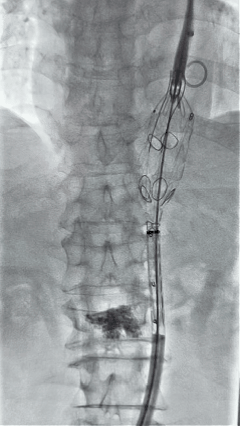

4. 经长鞘导入导管后,超选入腹腔干动脉,送入先健覆膜支架10*80mm一枚,近端重叠内分支,远端重叠腹腔干动脉,并予以10mm球囊后扩,手推造影显影良好。

3.gif

5. 撤出腹腔干导丝导管,经左肱动脉长鞘继续抓捕预置导丝将长鞘超选至另一侧内分支,后超选进肠系膜上动脉,沿导丝送入先健覆膜支架10*100mm一枚,近端重叠内分支,远端重叠于肠系膜上动脉,并予以10mm球囊后扩,手推造影显影良好。

8.gif